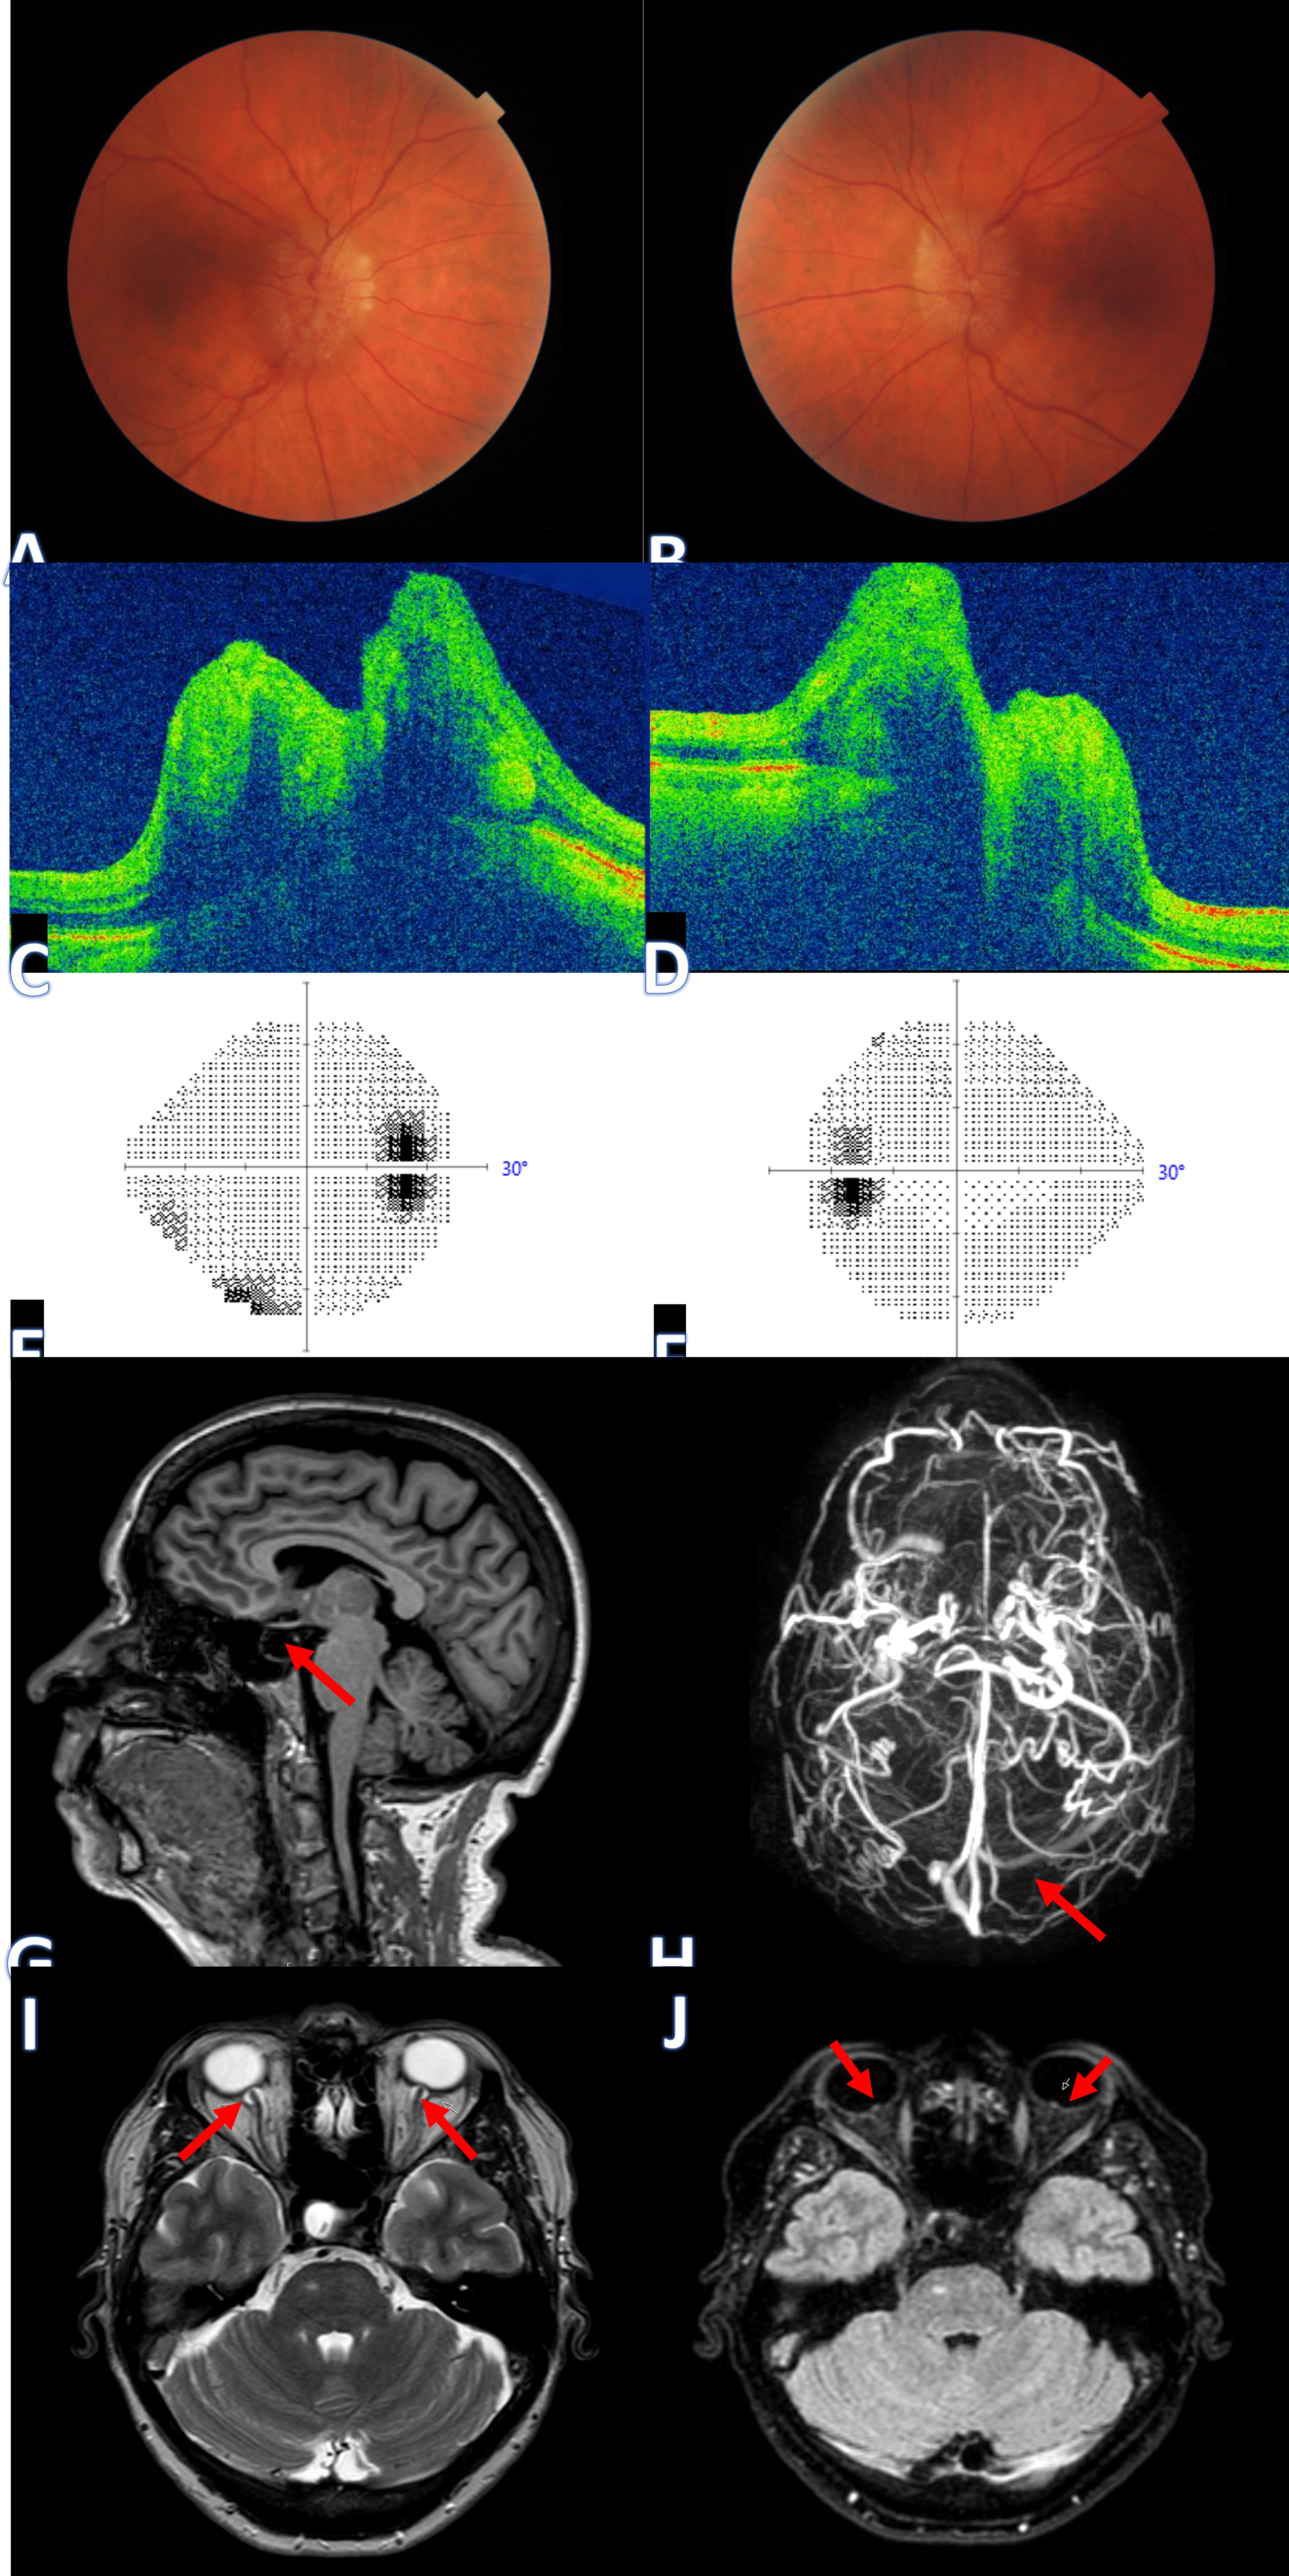

A 65-year-old woman presented with a case of IIH displaying symptoms of chronic headaches, transient visual loss upon postural changes (typically lasting seconds), and pulsatile tinnitus. Examinations revealed several key findings: bilateral papilledema (A and B), evident optic nerve head swelling in an OCT cross-section, notably more pronounced swelling in the nasal borders (C and D), an enlarged blind spot observed in the visual field (E and F), and an empty sella seen in the sagittal view of MRI (G). Additionally, MRA/MRV showcased the absence of signal in the right transverse vein sinus (H), contrasting with a clear signal in the left side (highlighted by a red arrow). Further observations included enhancement (with gadolinium) of the prelaminar optic nerve, distension of the perioptic subarachnoid space, and tortuosity of the orbital optic nerve (I), along with intraocular protrusion of the prelaminar optic nerve (J). (Image courtesy of J. Khadamy)